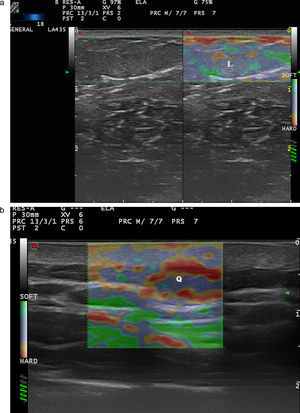

Elastografía de la patología inflamatoria cutáneaAl igual que la inflamación produce cambios en la estructura ecográfica en modo B y en el Doppler de la piel y los anejos36, esta inflamación también influye en el grado de dureza de estas estructuras7 (fig. 8).

En el estudio de Gaspari et al.37 se estudiaron 50 pacientes con abscesos que acudían a urgencias para drenaje, en modo B y mediante SE. La elastografía permitió observar áreas de rigidez alrededor de los abscesos que no eran evidentes en modo B.

En epidermis y dermis, el grupo de Cucoş et al.38 midieron los efectos de los corticoides tópicos en el grosor de la epidermis y la dermis, así como en la elasticidad en 16 placas de psoriasis. El grosor epidérmico disminuyó, mientras que la dermis incrementó ligeramente de grosor sin variar la elasticidad de la placa. Estos resultados, pese al limitado número de pacientes, parecen indicar la escasa sensibilidad de la SE en el tratamiento de las placas de psoriasis.

La elastografía ha tenido un mayor desarrollo en los procesos fibrosantes o esclerosantes primariamente cutáneos o sistémicos (morfea/esclerodermia), en los que las escalas de medida clínica presentan una sensibilidad y especificidad muy limitadas39 (fig. 9).

Los estudios iniciales realizados en elastografía SE de la esclerodermia, como el de Iagnocco et al.39, indicaban que la dermis de los pacientes con esclerodermia presentaba una rigidez mayor que la de los controles. Sin embargo, la reproducibilidad de la técnica en otras localizaciones como los dedos era variable, quizá por la cercanía de la superficie ósea de las falanges. Di Geso et al.40 repiten esta misma experiencia para comprobar el índice de concordancia en SE y en modo B. Los autores llegan a la conclusión de que la elastografía disminuye la variabilidad inter e intraobservador en la valoración del grosor de la dermis de los dedos en los pacientes con esclerodermia.

La afectación de la región perioral en pacientes con esclerosis sistémica es frecuente41. Cannaò et al.41 describen en un estudio piloto una escala elastográfica según segmentos periorales en la que demuestran que la dureza perioral es mayor en los sujetos con esclerodermia que en los controles.